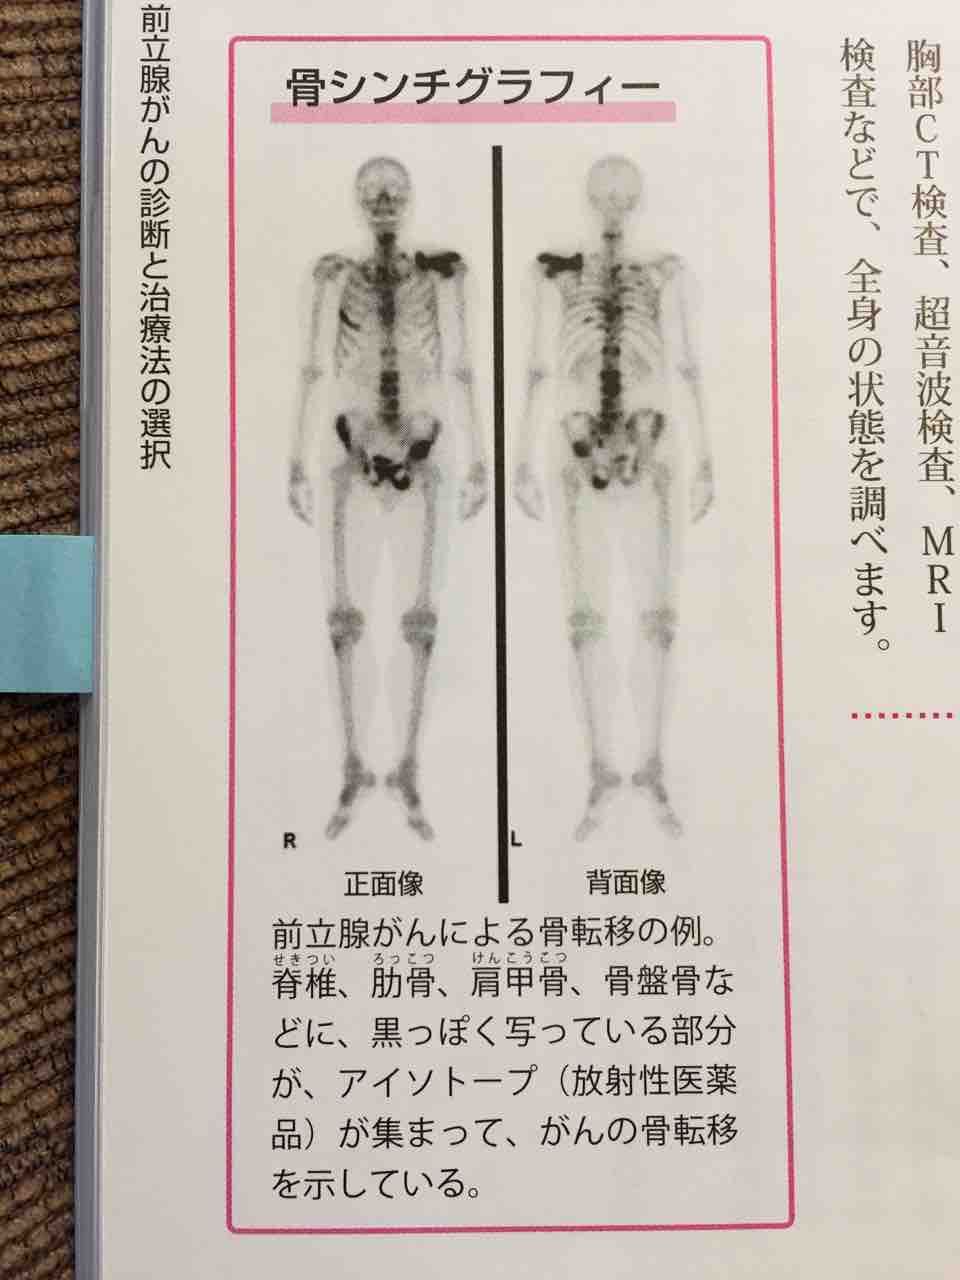

全身骨シンチグラフィ 乳癌 肺癌 前立腺癌等の骨転移病巣の検出

前立腺がんの検査 骨シンチグラフィー 前立腺がんの治療と名医

主な核医学検査 骨 骨シンチグラフィ 核医学検査のご案内 医療関係者

前立腺がんの検査 画像検査 Ct Mri 骨シンチグラフィ で何がわかる

全身骨シンチグラフィ 乳癌 肺癌 前立腺癌等の骨転移病巣の検出

骨シンチグラフィによる骨転移の診断 Bone Scan Ct Mri画像診断